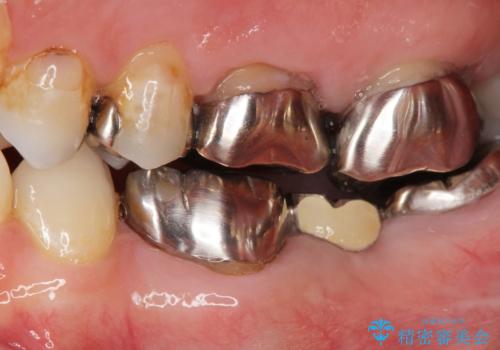

- 矯正治療・銀歯のやりかえ希望で来院されました。

矯正治療により歯並びの改善を行いつつ失われた最後方臼歯をインプラントを用いて咬合機能回復します。

- 40万円(ストローマンインプラント・カスタムチタンアバットメント・メタルボンドクラウン)費用は治療当時の料金となります